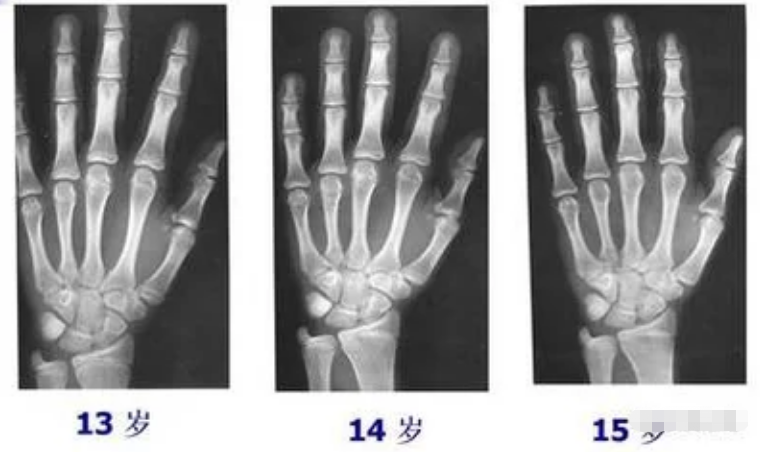

什么样的叫骨骺线闭合

1、骨骺线闭合是指长骨两端软骨结构停止增殖和骨化,导致骨骼纵向生长终止的生理过程其核心机制与影响如下1 基本定义与结构骨骺线位于长骨的骨骺与干骺端之间,由软骨组织构成,是儿童青少年身高增长的关键区域软骨细胞通过持续分...